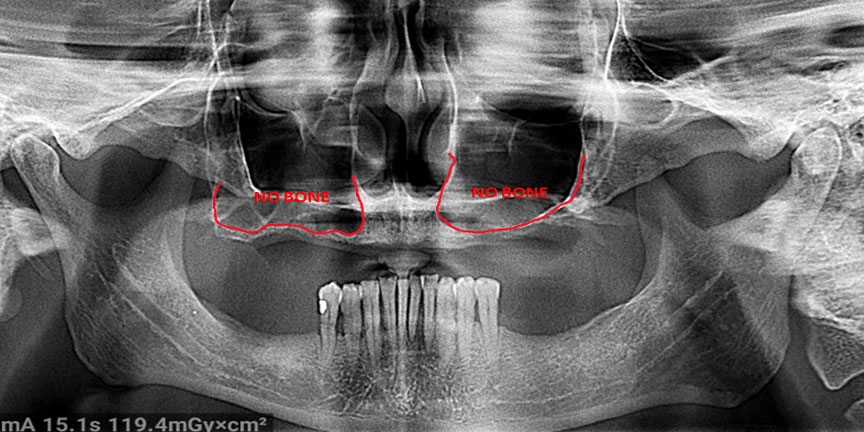

Difficult Cases

- We treat patients when other providers cannot manage.

Severe Bone Loss